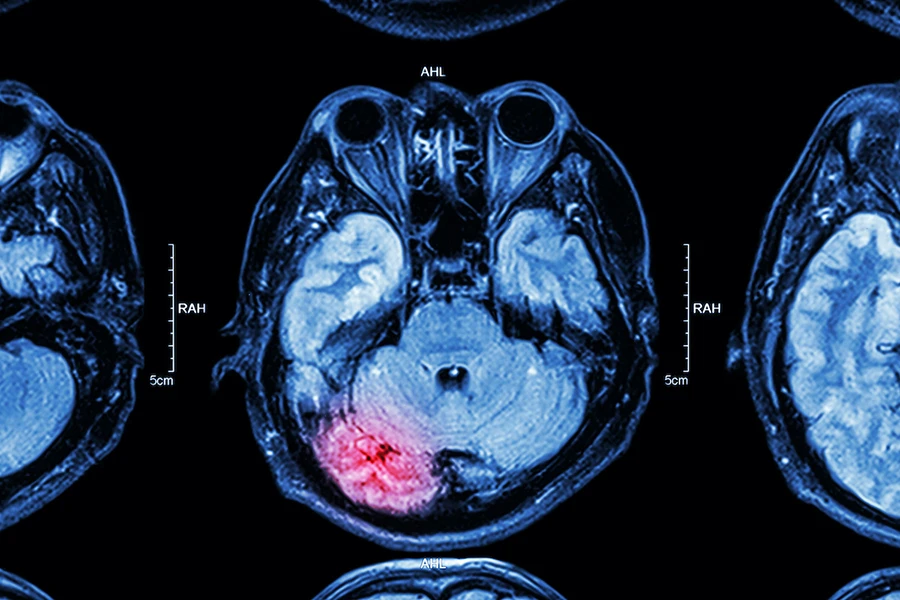

When physicians make their diagnosis of a TBI, they will rate it in severity based on how long the patient has been unconscious and whether the injury shows CT or MRI changes.

- For severe TBIs, there is a loss of consciousness for over one full day and there are typically changes on head CTs or brain MRIs.

When the head CT and/or brain MRI is normal, regardless of severity grade, these are categorized as ‘uncomplicated’. When there is a change in head CT and/or brain MRI, usually due to bleeding, these are categorized as ‘complicated’.